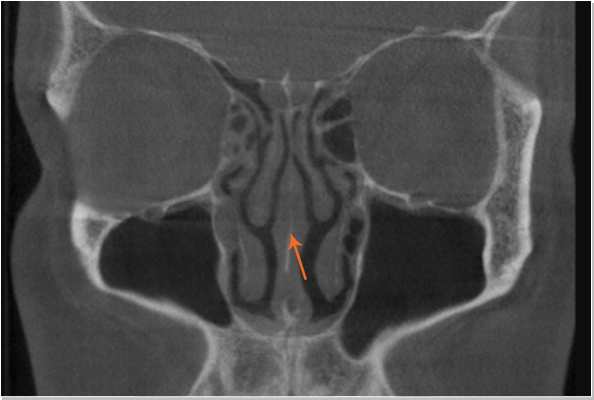

• 비중격만곡증 비정상

수술 전 철저한 분석으로 코의 외적인 부분(안장코)뿐만 아니라 코의 기능(비중격만곡증, 비염, 축농증 등)도 생각한 수술

코의 내부구조

약해진 비중격

이전 수술로 약해진 코

이전의 비중격 수술로 인하여 비중격이 없어 부득이 귀연골로 코 끝을 만듦

절골술 등을 이용하여 콧등을 바르게 펴고 고어텍스로 마무리 함